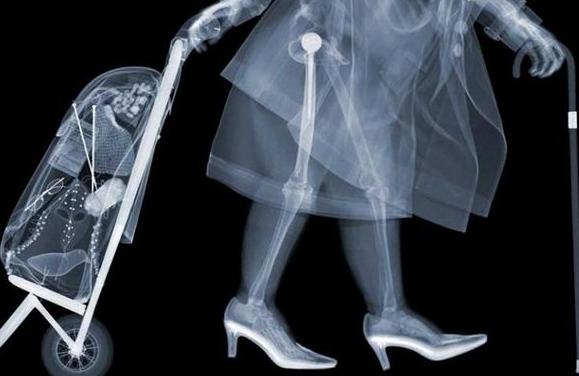

X射线-----相当于把蛋糕压扁检查

原理:X光穿过人体,不同部位吸收射线,底片上不会曝光或部分曝光,洗片后这个部位就是白色的。

优点:快捷、价廉。

缺点:受制于深浅组织的影像互相重叠和隐藏,有时需要多次多角度拍摄X光片才能看清。

X射线是著名的伦琴发现的,它是影响医学的开端。X线发明的故事大家也都熟悉,伦琴在一个偶然的机会下从X射线现中看见了自己手的骨骼。所以说X射线主要是用来看骨头。

此外还有一个最常见的作用是拍胸片,主要是粗略的看一下肺部和心脏的轮廓。一些诸如肺部感染,先天性心脏病导致心脏的大小形态变化,还有肺癌之类的典型的影像表现还是可以一目了然。还有人问什么透视和拍片有什么区别。简单的说透视就是医生在X光下看一眼,拍片就是把片子打印出来。